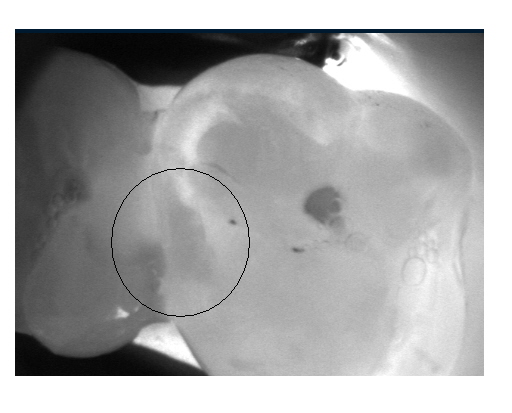

Zur professionellen Vorsorge gehört unserer Ansicht nach auch eine umfangreiche Diagnostik. Diese versuchen wir mit technischen Hilfsmitteln auf den neuesten Stand der Technik zu halten. So haben wir nun auch mit der DiagnoCam ein Hilfsmittel zur strahlungsfreien Kariesdiagnostik..

Mit der neuen DiagnoCam kann mittels Licht zwischen die Zähne geschaut werden.

Hier ein klinisches Beispiel aus der Praxis: Man kann die Kontaktpunktkaries gut erkennen , die aber röntgenologisch nicht eindeutig festgestellt werden konnte. Die Diagnocam bietet eine  gute strahlungsfreie Diagnosealternative.